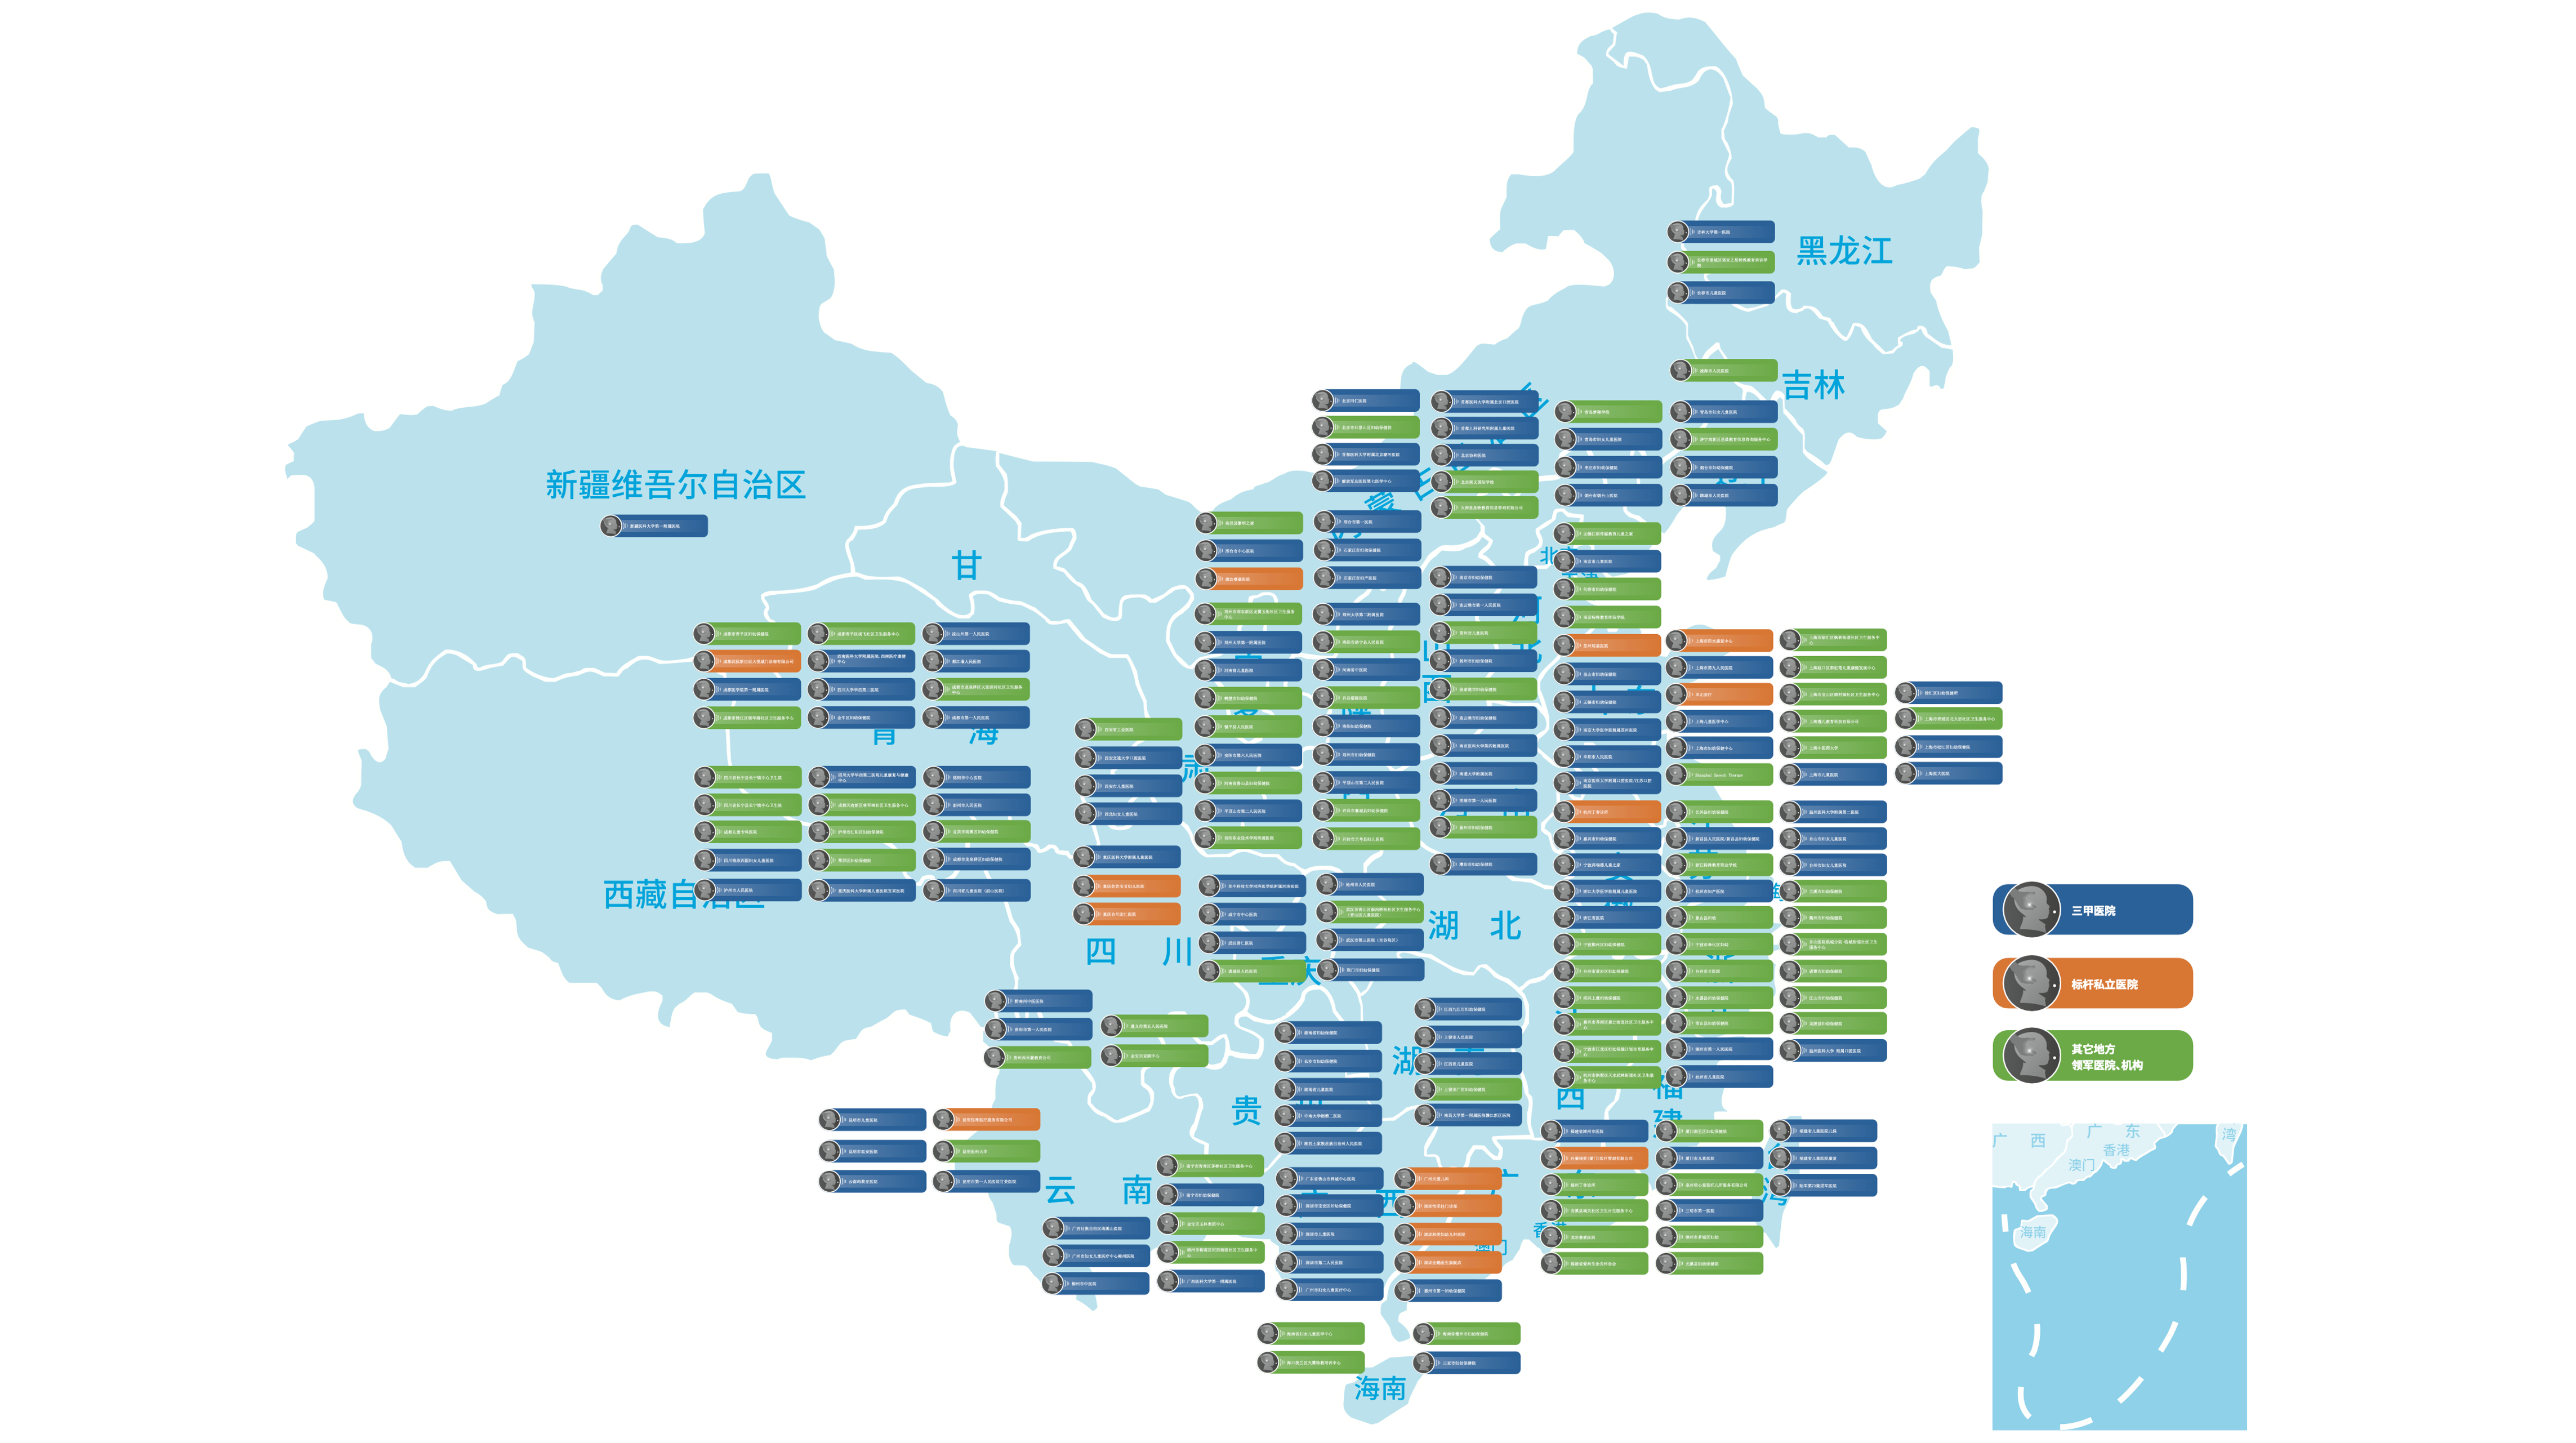

Bethel’s established network already spans 300 top Tier-3A hospitals across China.